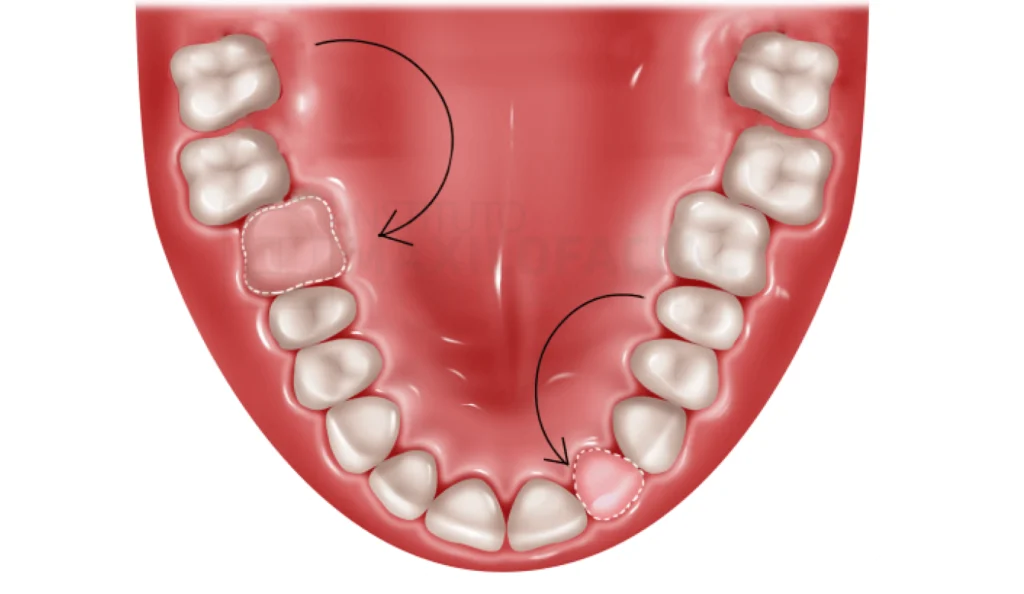

C’est une ancienne technique de valorisation chirurgicale qui remonte aux années 1960. Il s’agit d’extraire une dent de faible importance afin de remplacer une dent absente dans un secteur à haute valeur ajoutée.

Une personne peut avoir perdu une dent suite à un traumatisme, une infection etc… Nous réalisons dans un premier temps une radiographie panoramique ainsi qu’un scanner dentaire afin de trouver la dent donneuse. Nous allons extraire cette dent afin de la réimplanter à l’endroit de la dent manquante.

- Chez l’adolescent, il est impossible de remplacer une dent manquante par un implant dentaire. Un implant ne se met que chez l’adulte ayant terminé sa croissance. Nous prélevons une dent immature, nous la réimplantons, puis cette dent va continuer sa croissance car l’organisme la reconnait comme telle. Il y aura ensuite un travail esthétique afin de lui donner le même mimétisme que la dent perdue.